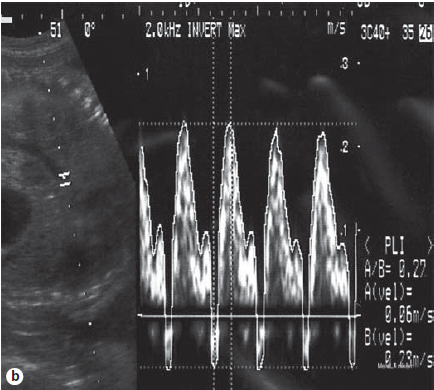

孕29+4周行胎儿腹腔穿刺术抽出20ml液体,做直接镜下观,可见鳞状细胞,怀疑胎粪性腹膜炎 孕30+6周行胎粪性腹膜炎的治疗 超声提示胎儿有大量腹水和腹部钙化灶以及阴囊肿块 且有羊水过多 行第二次穿刺术,抽出60ml液体 使用盐酸利托君进行早产阵痛的治疗 穿刺术后一天,前负荷指数降到正常 然而,31+6周时,由于胎儿腹水再一次增加,前负荷指数又上升到0.52 于是行第三次穿刺术,抽出65ml液体 一天后,前负荷指数又降到正常 第三次穿刺术后胎儿腹水没有复发 前负荷指数也没有再升高 羊水体积也保持正常